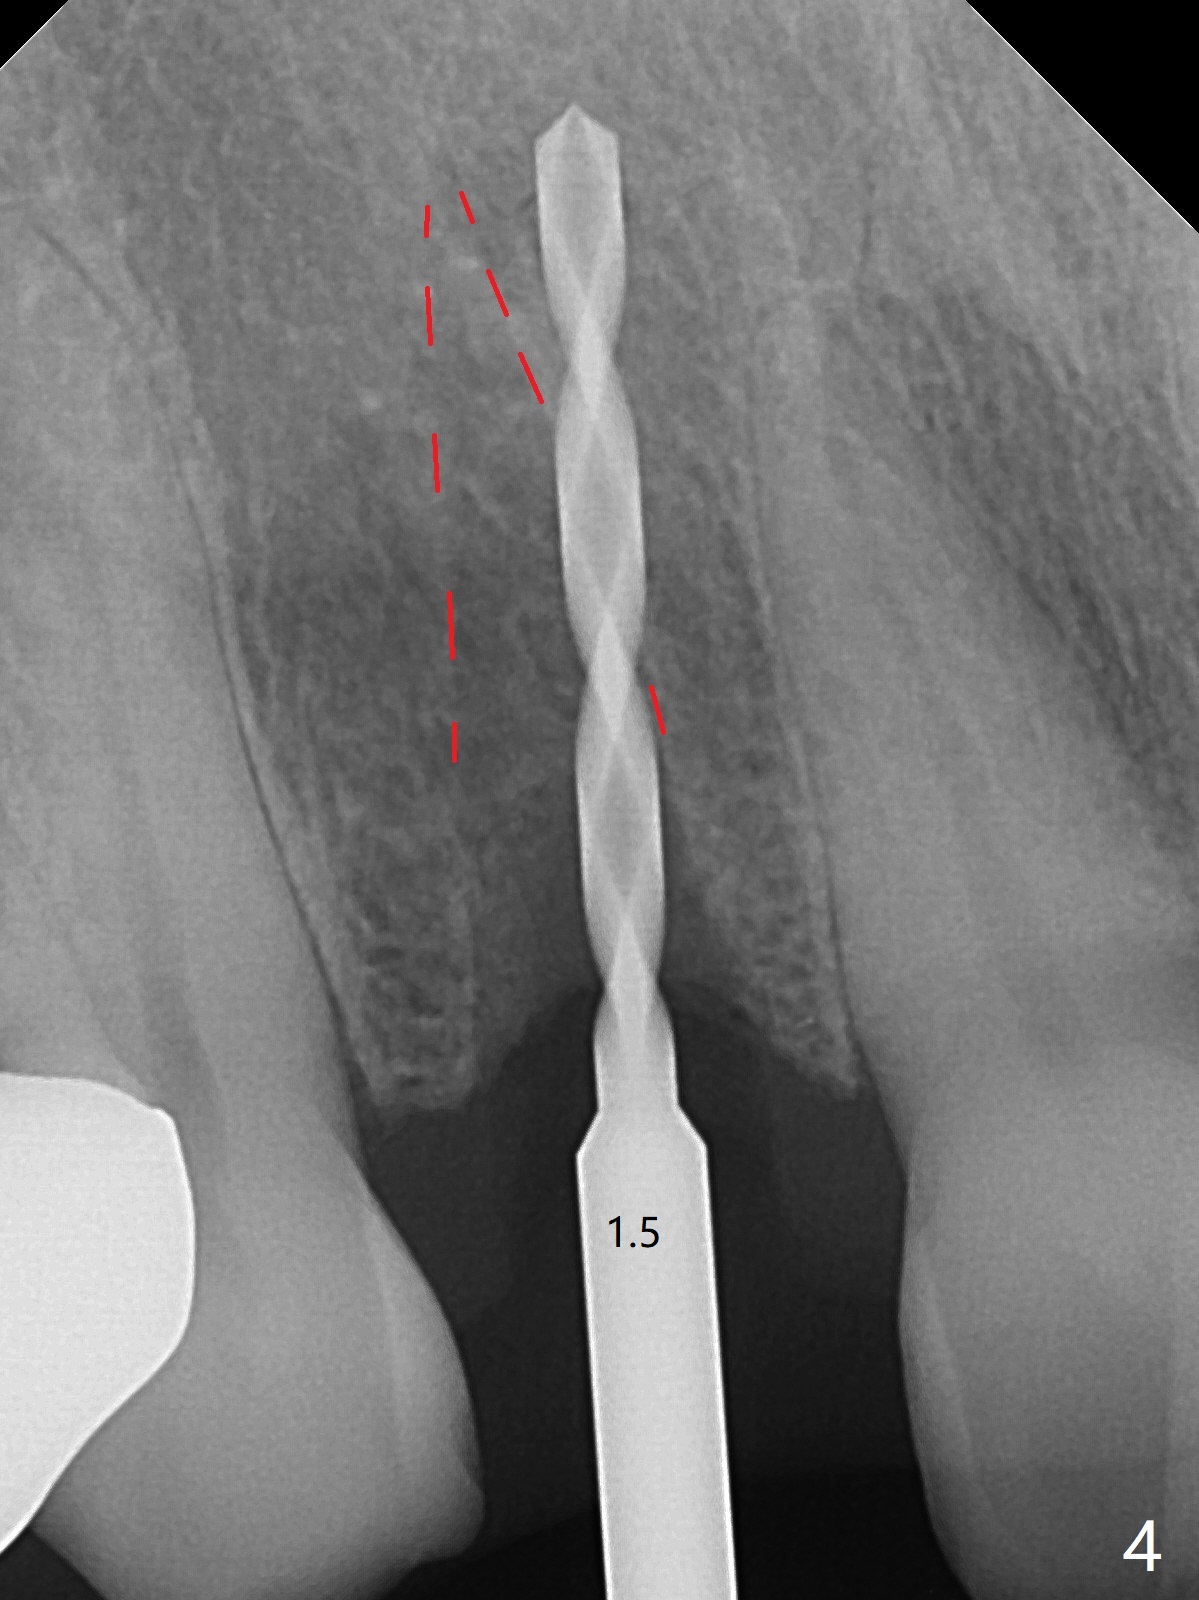

The rebonded crown at #7 debonds in a few days. There is deep anterior overbite and buccal concavity (Fig.1 *). The equigingival fracture (Fig.1,2) seems difficult to restore considering lack of posterior support (lower RPD in Fig.1). Buccal shield is tried in spite of the long root. It is not easy to tell whether the infected apex is removed due to the deep socket. In fact the apical buccal plate perforates because of use of surgical handpiece. Finally the buccal shied is removed. PA confirms the retained apex (Fig.3 *). The initial osteotomy with 1.5 mm drill in place is off trajectory (Fig.4). After adjustment of the trajectory of osteotomy (Fig.5), a 3x16(2) mm 1-piece implant is placed within normal limit (10-15 Ncm, Fig.6)). In fact bone graft is placed before (Fig.6,7 arrowhead; to repair apical buccal plate perforation) and after (Fig.6 *) implantation. The gingiva (including papillae) remains normal around the provisional 3 months postop (Fig.8). The bone graft becomes more organized 3 months postop (Fig.9), continues to do so 4.5 months postop (Fig.10) and becomes dense coronally 9 months post cementation (Fig.11: *).